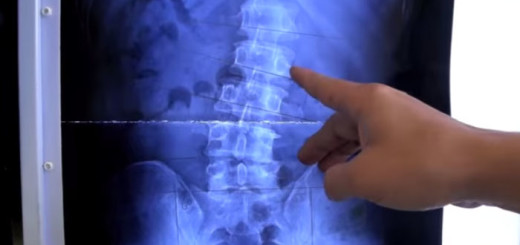

Chronic lower back pain

This patient was complaining of middle and lower back pain. All that he required was a right ileum correction.